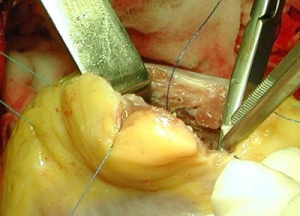

Вскрывается просвет огибающей артерии

Накладывается анастомоз аутовенозного шунта с огибающей артерией